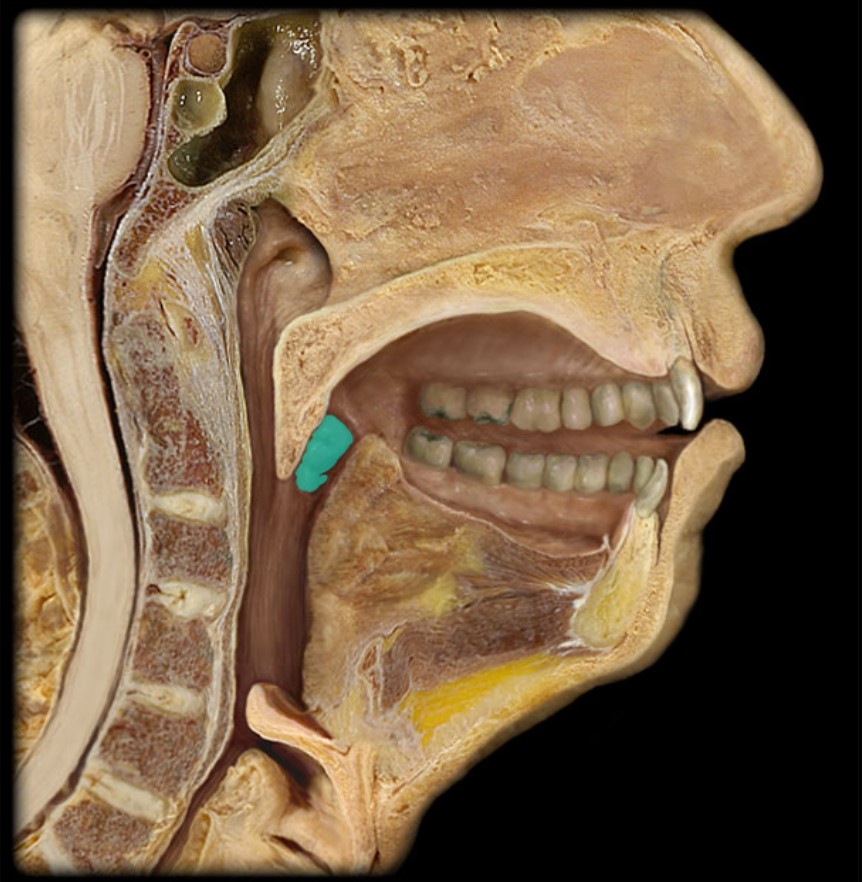

Anatomy 5 - Bifurcated Skull

29 Terms

1

New cards

Thyroid Gland

(Donor Only)

2

New cards

Atlas

3

New cards

Vertebral Artery

(Donor Only)

4

New cards

Nasal Septum

(Donor Only)

5

New cards

Esophagus

6

New cards

Trachea

7

New cards

Vocal Fold

8

New cards

Epiglottis

9

New cards

Hyoid

10

New cards

Mandible